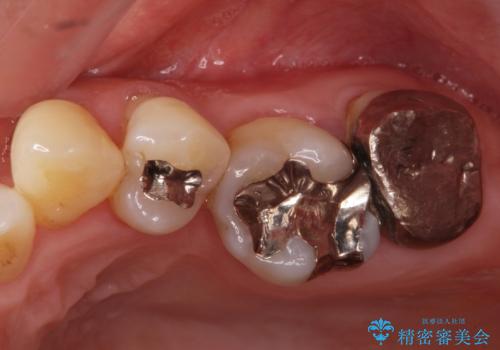

銀歯を白くしたいセラミック治療。

- 奥の銀歯を白くしたいとの事で来院。

痛みはないとの事でしたがレントゲンを撮影したところ根の先に病巣がある事がわかりました。

被せ物、古い材料を徹底的に除去し、ラバーダム防湿にて無菌的処置を行い、セラミックの被せ物で治療を行いました。